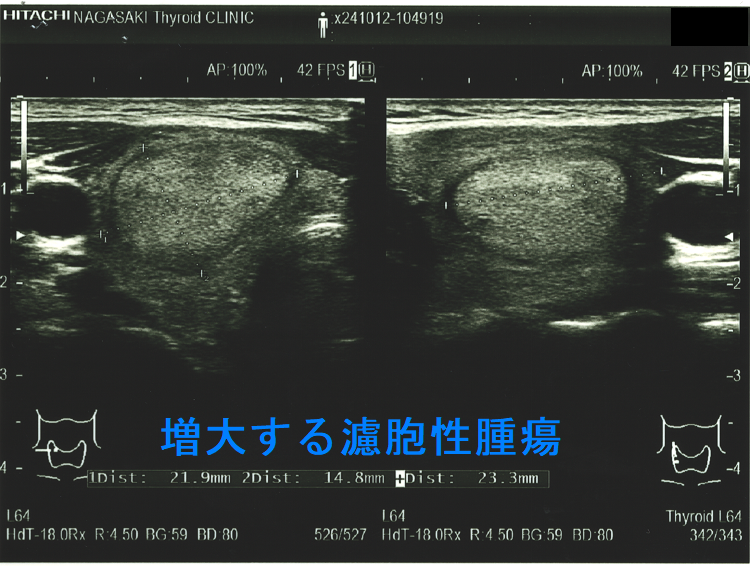

逆に、甲状腺乳頭癌に見えるが腺腫様結節の場合もあります。